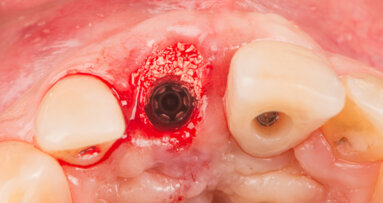

Straumann has obtained exclusive distribution rights in most major markets for Z-SYSTEM’s next generation implant line, which complements their current PURE Ceramic Implant system. The new implant has a bone-level, two-piece design for prosthetic flexibility and convenient handling. Unlike other implants, it features a ceramic connection screw, making it the first two-piece, screw-retained dental implant to be completely metal- and plastic-free. Straumann plans to launch the new line in 2019.

Placing an implant immediately after tooth extraction offers several advantages, including a reduced treatment time, fewer surgical sessions, possibility of...